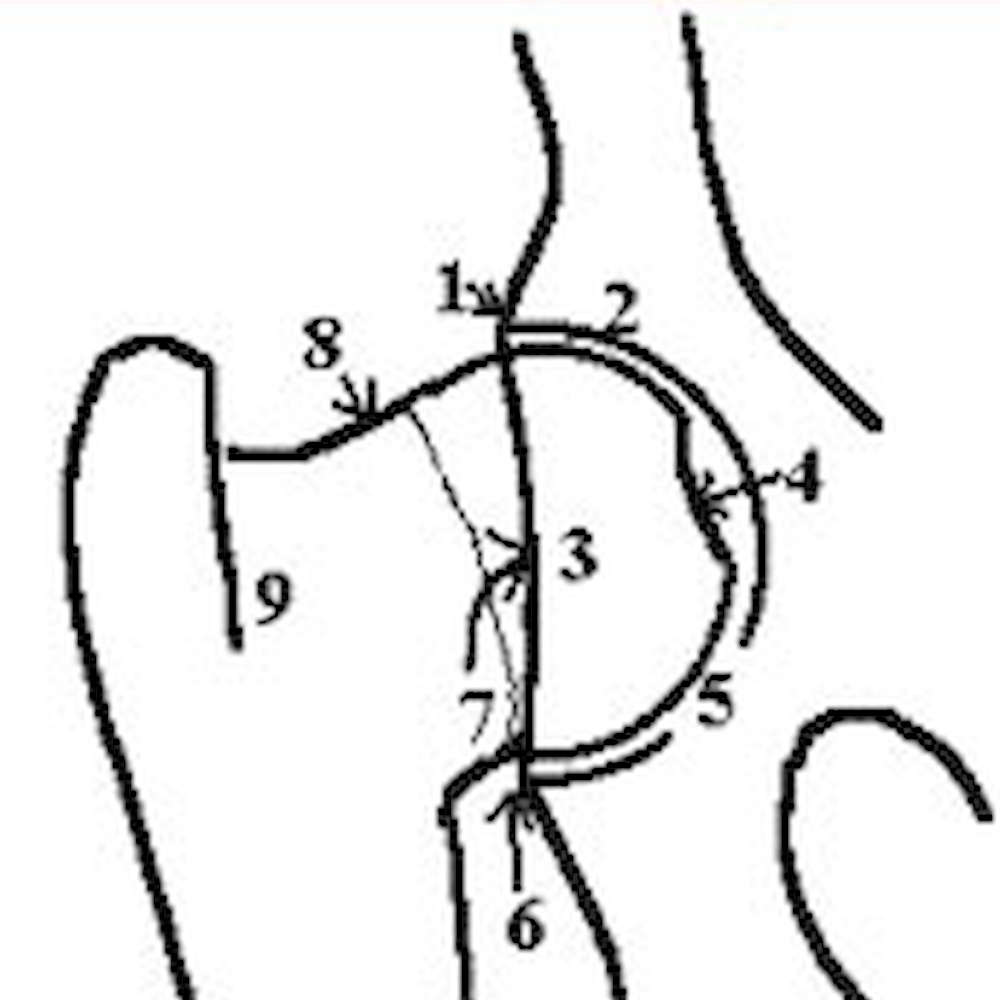

Radiographs of animals 24 months of age or older are independently evaluated by three randomly selected, board-certified veterinary radiologists from a pool of 20 to 25 consulting radiologists throughout the USA in private practice and academia. Each radiologist evaluates the animal's hip status considering the breed, sex, and age. There are approximately 9 different anatomic areas of the hip that are evaluated.

Craniolateral acetabular rim

Cranial acetabular margin

Femoral head (hip ball)

Fovea capitus (normal flattened area on hip ball)

Acetabular notch

Caudal acetabular rim

Dorsal acetabular margin

Junction of femoral head and neck

Trochanteric fossa

The radiologist is concerned with deviations in these structures from the breed normal. Congruency and confluence of the hip joint (degree of fit) are also considered which dictate the conformation differences within normal when there is an absence of radiographic findings consistent with HD. The radiologist will grade the hips with one of seven different physical (phenotypic) hip conformations: normal which includes excellent, good, or fair classifications, borderline or dysplastic which includes mild, moderate, or severe classifications.